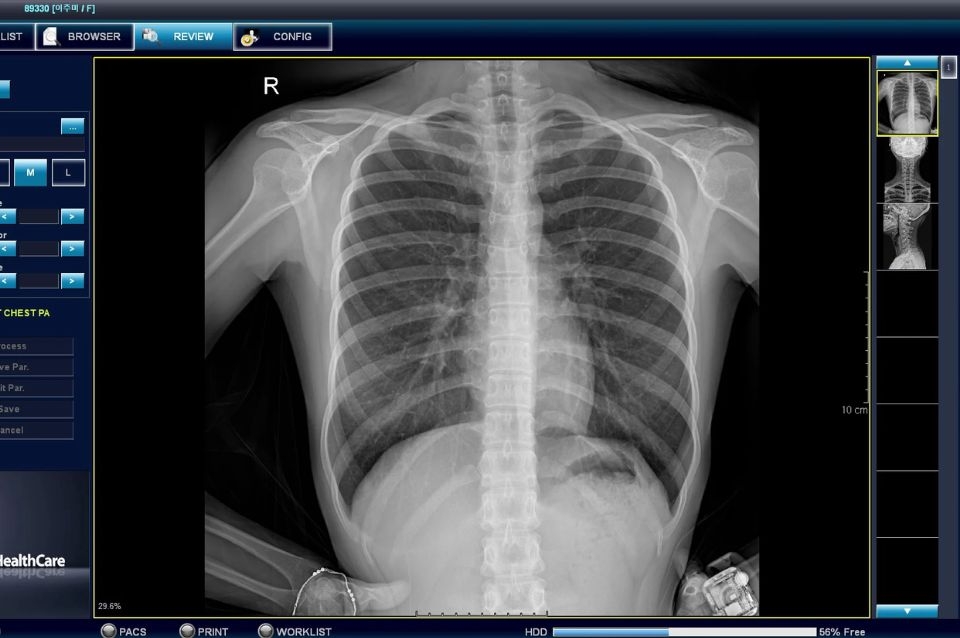

Provincia licita la compra de equipamiento radiográfico para 40 efectores

Este martes a las 10.30, en el Ministerio de Salud, se llevará a cabo la apertura de sobres con las ofertas económicas para digitalizadores de placas radiográficas. El presupuesto oficial es de $ 876.000.000.

El Gobierno de la Provincia de Santa Fe, a través del Ministerio de Salud, llevará a cabo la apertura de sobres con las ofertas económicas correspondientes a la licitación de 40 digitalizadores de placas radiográficas, para efectores del segundo nivel. El presupuesto oficial es de $ 876.000.000.

Se trata de una compra importante que realizará el Ministerio de Salud y que permitirá actualizar la tecnología para la obtención de imágenes de radiografía. En esta primera etapa se alcanzará al 50 % de los efectores de segundo nivel que todavía utilizan revelado convencional, con insumos costosos y cada vez menos disponibles en el mercado. Entre otros beneficios se incorpora tecnología “limpia”, que además permite obtener la imagen digital en menos tiempo que el método tradicional de revelado y ofrece una mejor calidad para el diagnóstico.